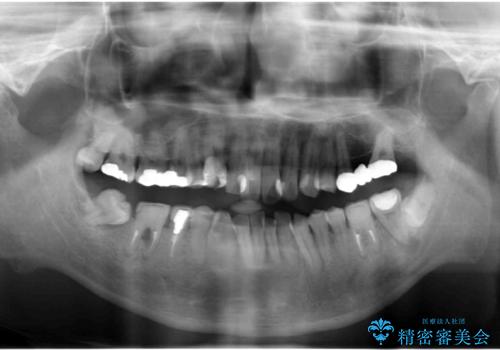

- 短期間で歯並びを治したいとのこと。期間が短ければセラミックでかぶせる治療できれいにするのでも構わない。虫歯の治療もすべてお願いしたいとのことでした。

右下の奥歯は残せない可能性を説明しました。

また、歯並びの矯正をするのではなければ、右上の八重歯は、犬歯を抜くか、奥に入っている歯を抜くかになるとお伝えしました。結果、根の長い犬歯を残して右上の前歯を抜歯しブリッジにしました。また、前歯の神経は極力取らないで治療を行いました。(結果神経を取る治療は前歯には行っておりません)

右下奥歯二本はインプラントにしました。(横浜桜木町歯科院長 大元先生による)

また、銀歯はすべてやり直しを行い、セラミックでやり替えを行いました。